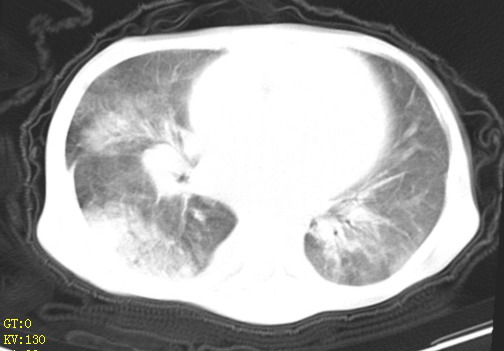

女,12岁,气促、咳嗽2天,3个月前查胸片示:两肺感染,急诊入院查ct,血常规等未检查。

双肺中下野不规则片絮状阴影,中外带明显,双侧胸腔少量积液,心影增大,心腔密度减低,隆突下及左侧气管旁见钙化淋巴结影,考虑双肺感染、心衰;建议结合临床除外h1n1并急性心衰,先心不能排除。

两肺多发片絮状模糊影,以下肺外带居多,内见支气管气像,纵膈窗未减影,两侧胸腔积液,心影增大,结合心超,支持重症肺炎,非常时期,甲型h1n1流感不排除。